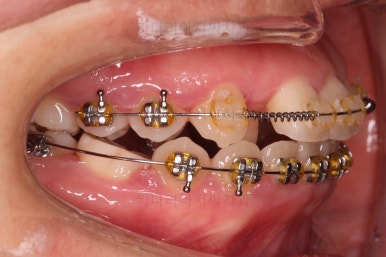

미니스크류가 등장했네요.

아랫니는 아무 생각 없이 당기기 해주면 앞니가 너무 들어가 입이 합죽해질 수 있으니 앞니가 들어가는 양을 조절하기 위해서 미니스크류를 사용해주어요.

적절한 시기부터는 어금니만 100% 앞으로 당겨와야 했기 때문이죠.

비슷한 방법으로 계속 당기기를 해줍니다.

이 과정이 매우 어렵고 시간도 많이 걸려요.

보통 유치 어금니를 뽑고 어금니만 거의 대부분 앞으로 당겨와야 하는 상황에서는 3년 혹은 그 이상도 보셔야 한다고 말씀 드리는 편이에요.

특히 이번 환자분은 저희 치과에 내원을 하기 전에 이미 1년 정도 교정치료를 하신 상태라 이원해서 치료를 하는 키다리아저씨치과의 입장에서도 마음이 조금 조급해지긴 했어요.

유치 발치와 어금니를 당겨오는 과정을 키다리아저씨치과에 내원하신 이후로 진행했기 때문이죠.

치아의 중앙선과 입매도 수시로 체크해 주고요.